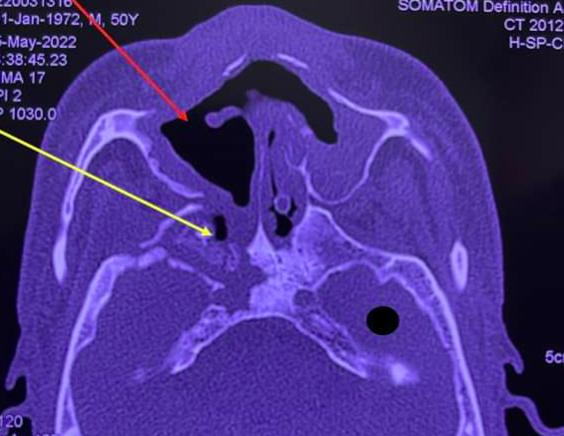

Trong thời gian vừa qua, Bệnh viện Răng hàm mặt Trung ương TP HCM và Bệnh viện Chợ Rẫy có ghi nhận chùm ca bệnh hoại tử xương sọ - mặt (24 trường hợp) trên bệnh nhân có tiền sử mắc Covid-19. Các ca bệnh này liên quan đến thiểu dưỡng cục bộ của xương sọ - mặt và bội nhiễm với nhiều nguyên nhân khác nhau, cần được nghiên cứu thêm.

Các ca bệnh này liên quan đến thiểu dưỡng cục bộ của xương sọ - mặt và bội nhiễm với nhiều nguyên nhân khác nhau, cần được nghiên cứu thêm. Ảnh minh họa.

Khi xuất hiện các triệu chứng trên, cần thực hiện hội chẩn các chuyên khoa liên quan, chụp cắt lớp vi tính là phương tiện tốt nhất để chẩn đoán sớm hoại tử xương sọ - mặt. Về điều trị, cần phối hợp các chuyên khoa liên quan, phẫu thuật loại bỏ các tổ chức hoại tử.

Đặc điểm chung của các ca bệnh là từng mắc Covid-19 từ 6-8 tháng; bị đau hàm, đau răng, sưng mắt, viêm xoang. Khi vào Bệnh viện Chợ Rẫy, vùng xương sọ, xương hàm trên của bệnh nhân đã hoại tử nặng nề, phải phẫu thuật bóc toàn bộ xương chết. Nhiều bệnh nhân có mủ bám trên xương sọ, màng não hoặc ghi nhận có nấm.